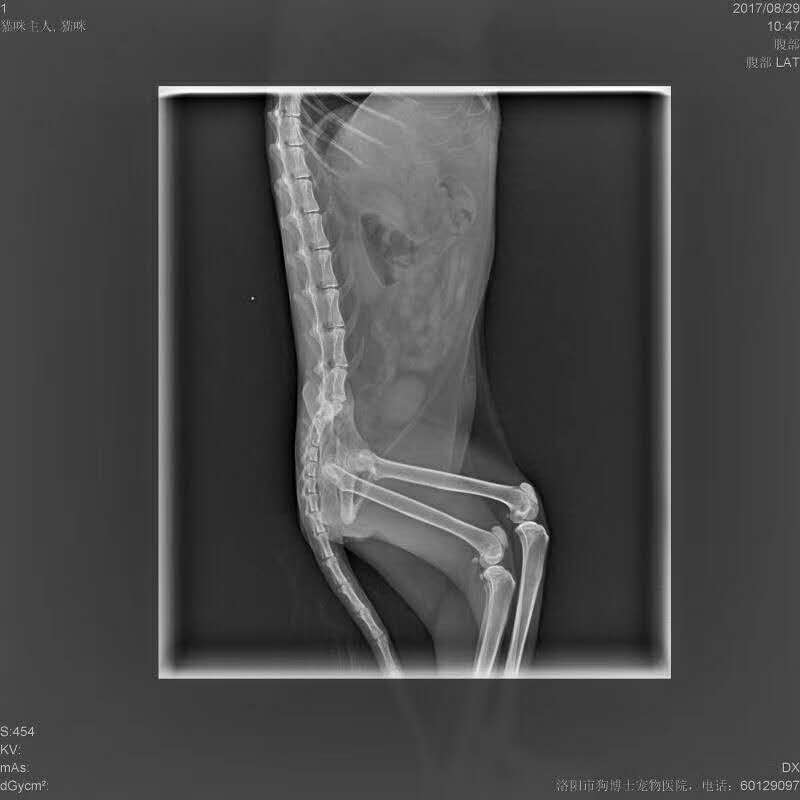

貓咪腸梗阻?絕育:貓咪,加菲貓混血兒,毛球引發(fā)腸梗阻,同時(shí)伴有嚴(yán)重肝臟,腎臟腫大(疑似長(zhǎng)期吃網(wǎng)購(gòu)貓糧引發(fā)),實(shí)施腸梗阻?絕育手術(shù),手術(shù)順利,但很擔(dān)心術(shù)后恢復(fù),體質(zhì)非常虛弱。